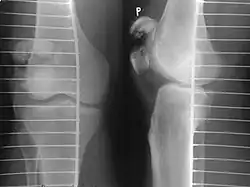

The patella can break in various ways depending on the way it is injured, and into two or more pieces.[1] Types include transverse, the most common, with one fracture line;[5] marginal; osteochondral; and the rare vertical type, or stellate, where a direct compression force gives rise to a comminuted pattern.[5][7] Patella fractures can be further classified as displaced, where the broken ends of bone do not line up correctly and separate by more than 2mm, or undisplaced and stable where pieces of bone remain in contact with each other.[1][7] If fragments of patella bone stick out from the skin it is known as an open patella fracture, and closed if the overlying skin is intact.[1]

Vertical patella fracture